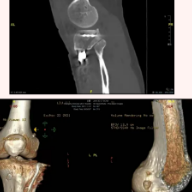

术后三维CT显示钢板及重建韧带的骨道位置良好

为及时有效地解除杨先生的病痛和烦恼,本部骨伤科一病区主任魏利成决定迎难而上,化繁为简,一次手术解决难题。魏利成通过对照检查结果并综合相关病情,为杨先生精心制定治疗方案:在关节镜引导下,精准实施前交叉韧带重建及内侧半月板后跟修复骨道,准确布置钢板螺钉位置,巧妙地避免了冲突,一次手术完美解决3个复杂创伤。